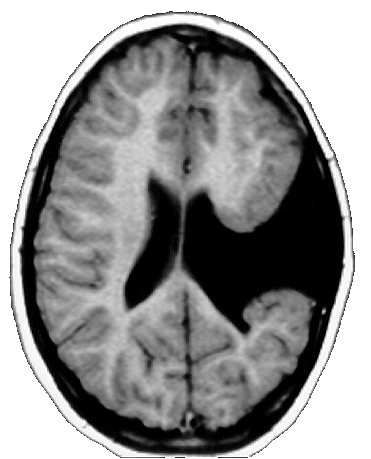

As crianças ARM e KTG são portadoras de lesões cerebrais denominadas Esquizencefalia (Fig. 5 e 6), que são decorrentes de distúrbios no processo embriogênico, que ocorrem no primeiro trimestre da gravidez. As lesões no indivíduo ARM se localizam no lobo frontal esquerdo e incluem também a ausência do septo pelúcido. Já a criança KTG tem as lesões localizadas no lobo parietal direito e também mostra sinais de comprometimento do hipocampo direito.

As lesões do indivíduo WA são do tipo Leucomalácia Multicística e se localizam principalmente no lobo parietal esquerdo. As lesões decorreram de problemas anóxicos perinatais, causados por problemas que a mãe experimentou alguns dias antes do parto. WA e ARM são canhotos e hemiplégicos à direita, e apresentaram atraso no desenvolvimento psicomotor. KTG é destra e tem hemiplegia à esquerda, apresentou também, atraso do desenvolvimento psicomotor.

Os MAREs de todos os indivíduos mostram uma atividade cerebral coerente com a lesão encontrada nas correspondentes MRIs. Assim, por exemplo, ARM tem uma lesão frontal esquerda na MRI, que está associada á um silêncio funcional nas derivações frontais esquerda nos seus MAREs (Fig. 5). Já o indivíduo WA tem uma lesão que se localiza predominantemente no lobo parietal esquerdo, que está associada a uma ausência de atividade nas derivações C3 e P3 nos seus MAREs mostrados na fig. 5. Finalmente, a lesão de KTG se localiza principalmente no lobo parietal direito, que se reflete nos correspondentes MAREs, por uma diminuição da ativação, principalmente, nas derivações P4 e T6.

O quadro eletroencefalográfico de KTG associado ao processamento verbal é totalmente distinto daqueles registrados nos indivíduos ARM e WA. Aqui observa-se uma ativação maior nas derivações F7, T3 e C3, no hemisfério esquerdo, durante as primeiras frases das charadas. Esta atividade se reduz um pouco na fase final da charada. Durante as duas etapas observa-se uma ativação de áreas frontais direitas, mas nunca das regiões temporoparietais do hemisfério direito.

As lesões de KTG se restringem ao hemisfério direito. Nesse caso, a participação do hemisfério esquerdo no processamento verbal fica claramente demonstrada nos MAREs apresentados na fig. 6. KTG é capaz de uma boa compreensão da linguagem, como demonstra seu bom rendimento nos jogos de linguagem. A pobreza de seu uso da linguagem expressiva está relacionado ao sua deficiência mental. Aliás, a inclusão de KTG nesse trabalho tem por finalidade apresentar um padrão de comparação para as crianças ARM e WA, também portadoras de deficiência mental. Dessa maneira, pode-se ressaltar que a plasticidade neural é a responsável pela capacidade de linguagem nessas duas crianças, e que a eventual pobreza do uso da linguagem que elas fazem, está mais associada à uma menor capacidade de processamento cerebral, devido à sua deficiência mental, do que às lesão específicas das áreas verbais do hemisfério esquerdo.